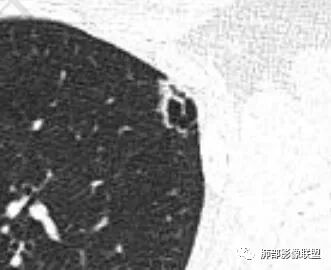

图太少了,不连续,都是切面问一句:大家不觉得是沿间质分布的吗?网格状吗肿瘤不考虑吧如果单独拿这一个出来,要警惕肿瘤

全部拿出来,好像就不符合

局限,内部密度低

空洞不太符合

结核不支持,结核,如果空洞,内部干净,壁光滑这个不符合考虑肺气肿合并感染

空洞不是

这种层面内部正常

看内部结构

密度稍低

我考虑肺气肿,是觉得内部纹理都在

只是稍膨隆,密度稍低高密度灶符合网状为主,所以朝肺气肿考虑